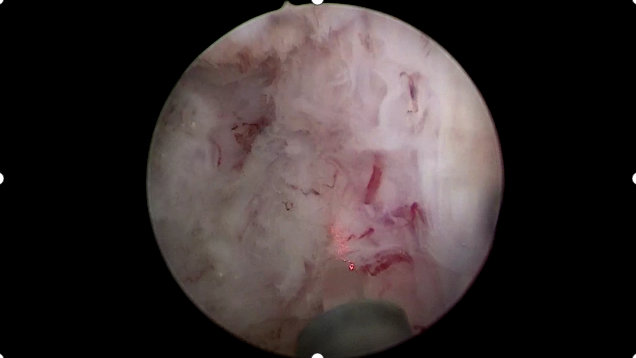

近日 贵州航天医院泌尿外科 成功为一名高龄 前列腺增生 患者实施 经尿道前列腺热蒸汽消融术 该技术的应用 为前列腺增生 并伴有多种基础疾病 无法耐受传统手术 的患者提供了新的治疗选择 对于许多中老年男性来说,本该安逸的晚年生活,却可能一直被一些“难言之隐”所困扰: ……我已经80多了,前列腺增生,自己没法拉尿,天天带个尿管,出行不方便,儿女又嫌弃,又有冠心病、又有肺气肿,医生说我心肺功能不好,不敢打麻醉,唉...怎么办? 这些问题,可能都与前列腺增生有关,不仅影响日常生活,也给人带来不小的心理负担,部分患者还可能因为年龄或身体其他状况,在选择治疗方案时感到顾虑重重。 针对前列腺增生带来的诸多问题,如今有了更优的微创治疗方式——前列腺热蒸汽消融术。 什么是前列腺热蒸汽消融术? 它是一种专注于改善前列腺增生所致排尿问题的微创治疗方式,整个过程类似一次“精准的蒸汽理疗”——医生借助一根纤细柔软的治疗探针,经人体自然通道抵达前列腺位置,向增生组织释放高温水蒸气,水蒸气在目标区域内快速释放能量,使部分增生组织发生改变,随后,这些组织会随着时间被人体自然吸收、逐步萎缩,从而减轻其对尿道的压迫,达到拓宽通道、改善排尿感受的目的。 前列腺热蒸汽消融术的优势 ※手术时间短:通常几分钟即可完成,过程便捷。 ※创伤小:经自然腔道操作,体表无切口,术后疼痛轻。 ※出血少:术中出血量一般较少,相关风险较低。 ※性功能保留好:注重保护相关结构与功能,减少对其影响。 ※适用人群广:尤其适合高龄或伴有其他慢性疾病的患者。 注:本文仅为医疗技术介绍,具体治疗方案请务必咨询临床医生,并结合患者个体情况制定。部分图片来源于网络,如有侵权,请联系删除。 贵州航天医院 泌尿外科专家简介 石 英 泌尿外科党支部书记、主任,主任医师 中国医师协会泌尿外科分会感染协作组委员,奥林巴斯泌尿系软镜西南区专家组成员,西南地区第一批输尿管软镜专家组成员,贵州省医学会泌尿外科分会委员,贵州省性学会理事,贵州省性学会常务委员,贵州省泌尿外科专业医疗质量控制中心专家委员会委员。 从事泌尿外科专业近30年,熟练掌握泌尿系各类疾病的诊治,具有丰富的临床经验,擅长泌尿系结石、腹膜后肿瘤及泌尿系肿瘤的手术治疗,对泌尿系感染、泌尿系结核、尿源性脓毒血症的救治有独到的见解及抢救经验,在贵州省率先引入输尿管软镜技术,同时在男科领域,对男性阳痿、早泄及前列腺疾病有很深的研究。 李国成 泌尿外科副主任,副主任医师 中国人体健康科技促进会男科学专业委员会委员,贵州省性学会泌尿外科分会委员,贵州省医学会男科学分会委员,遵义市医学会男科学分会副主任委员兼秘书长,遵义市医学会泌尿外科分会常务委员,贵州航天医院男科带头人。 从事泌尿外科及男科工作10余年,曾多次前往上海交通大学附属第一人民医院、中国中医科学院西苑医院进修学习男科;擅长性功能障碍的诊治、男性整形手术、前列腺增生激光手术、显微手术等。 李 凯 中共党员,泌尿外科副主任医师 贵州航天医院肿瘤腔镜组带头人,擅长肾癌根治术、输尿管癌根治术、膀胱及前列腺癌根治术、腹腔镜输尿管狭窄切除吻合术、输尿管切开取石术等手术,在遵义市率先开展泌尿系结核后膀胱挛缩全腹腔镜下膀胱扩大术。 贵州省医学会泌尿外科分会青年委员,遵义市医学会男科分会常务委员,遵义市医学会泌尿外科分会常务委员。 贵州航天医院泌尿外科简介 • ✦ 基本情况 ✦ • 贵州航天医院泌尿外科创建于20世纪60年代,经过几代人的努力,微创与内镜手术占比达90%以上,科室亚专业框架完善。是贵州省临床重点专科建设单位、北京清华长庚医院李建新教授团队诊疗及会诊中心、北京医学会尿路修复与重建诊疗及会诊中心、上海公济泌尿外科集团遵义中心、上海援黔专家李铮教授男科工作室、贵州省泌尿外科质量控制专家委员单位。 • ✦ 专科特色技术 ✦ • (一)泌尿系结石内镜碎石技术 泌尿系结石微创治疗领域方面是贵州省首家引进科医人钬激光碎石技术科室,在遵义地区率先掌握输尿管硬镜、软性镜,经皮肾镜钬激光碎石技术。目前是北京清华长庚医院泌尿外科“手把手”经皮肾镜碎石技术培训基地、贵州省输尿管软镜培训基地。 1.负压吸引可弯曲软镜鞘电子软镜碎石术 2.标准与超微通道相结合的经皮肾镜碎石取石术 (二)微创腹腔镜技术 泌尿外科腹腔镜技术师承于浙江省人民医院、北大、北京解放军总医院。目前采用经腹、经后腹双入路法的腹腔镜技术完成肾部分切除、肾切除、肾输尿管全长切除、肾盂输尿管成形、输尿管狭窄吻合、膀胱翻瓣等手术。在遵义地区率先掌握腹腔镜下膀胱癌根治术、腹腔镜下前列腺癌根治术。 (三)男科、盆底技术临床应用 遵义地区男科分会主委单位,是贵州省首家引进尿动力学检查并取得了全国资质认证科室,也是贵州省首家进行RigiScan检查的单位。在遵义地区率先掌握显微取精子技术以及显微镜下治疗精索静脉曲张、显微镜下输精管吻合、输精管附睾吻合技术。率先采用前列腺激光剜除术治疗前列腺增生症。在陆军军医大学西南医院泌尿外科主任沈文浩教授指导下,完成遵义市首例神经源性膀胱骶神经调节刺激器置入术。 • ✦ 诊疗范围 ✦ • 诊疗范围(除外肾移植、癌栓):泌尿系结石、泌尿系肿瘤、肾上腺疾病、肾积水、前列腺增生、男性生殖器功能障碍(精索静脉曲张、生殖道感染、输精管梗阻等)、盆底功能障碍性疾病(膀胱脱垂、排尿功能异常、尿失禁)、泌尿生殖系畸形。 泌尿外科拥有独立门诊治疗室、日间手术室、尿动力学检查室、精液分析检查室、男性勃起功能检查及治疗室、ESWL治疗室、结石分析检查室。